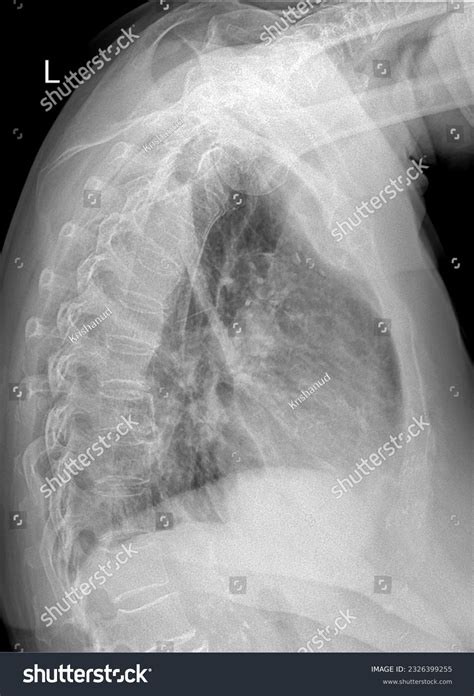

A Lateral Chest X Ray is a radiographic image taken from the side of the body, providing a different perspective compared to the standard anteroposterior (AP) or posteroanterior (PA) views. This lateral view is particularly useful for assessing the depth and position of structures within the chest, such as the heart, lungs, and diaphragm.

Interpreting a Lateral Chest X Ray requires a trained eye and knowledge of normal anatomy. Key structures to assess include:

• The heart and its borders

• The lungs and any visible abnormalities

• The diaphragm and its position

• The ribs and spine